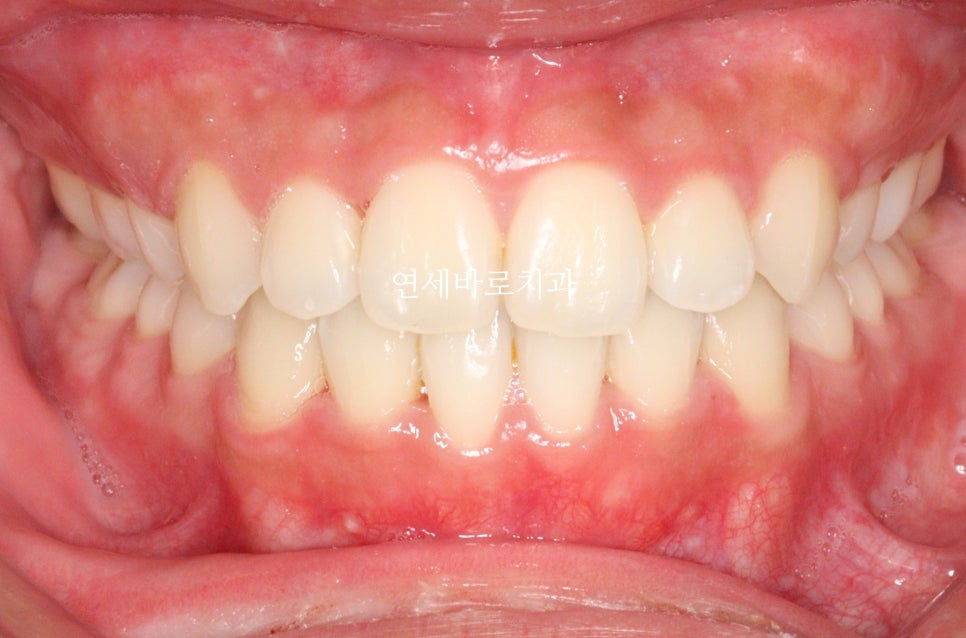

중간에 수술도 하시고, 수술 후에 교정치료를 더 진행하셨습니다.

그리고 22년 12월에 마무리 , 21년1월에 저희 병원에 처음 왔으니 2년이 조금 안되는 기간이 소요되었군요.

수술 환자분들은 장기적인 정기검진이 중요합니다.

최근에 오셨을때 모습입니다.

아쉽게도 처음 끝날때와는 약간은 다른 중심선을 관찰하였습니다.

하지만 좌우 교합은 긴밀하게 유지되고 있었고 안모의 변화 등 다른 부작용은 관찰되지 않았습니다.